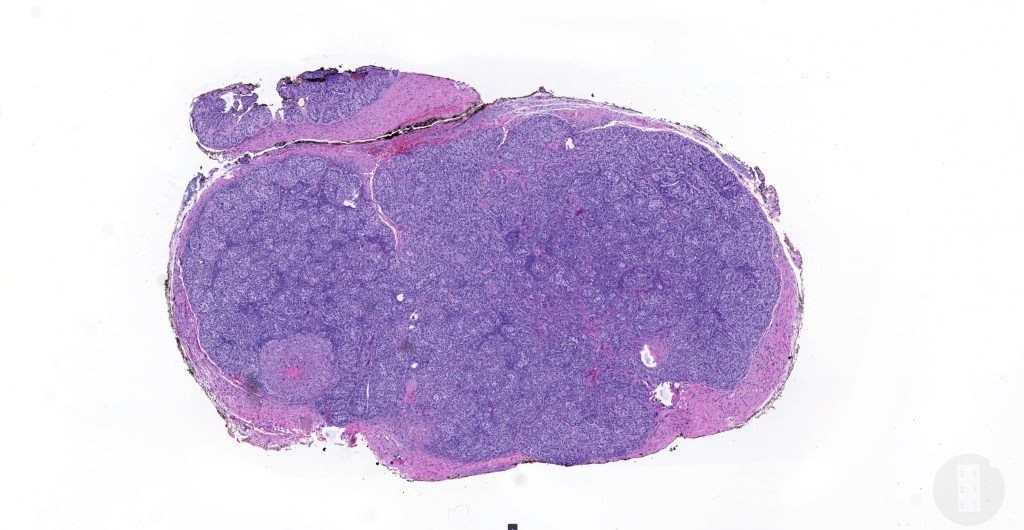

•Low grade trichoblastic carcinoma is easily recognized as trichoblastomatous but shows an infiltrating margin with deep involvement into subcutaneous fat +/- muscle